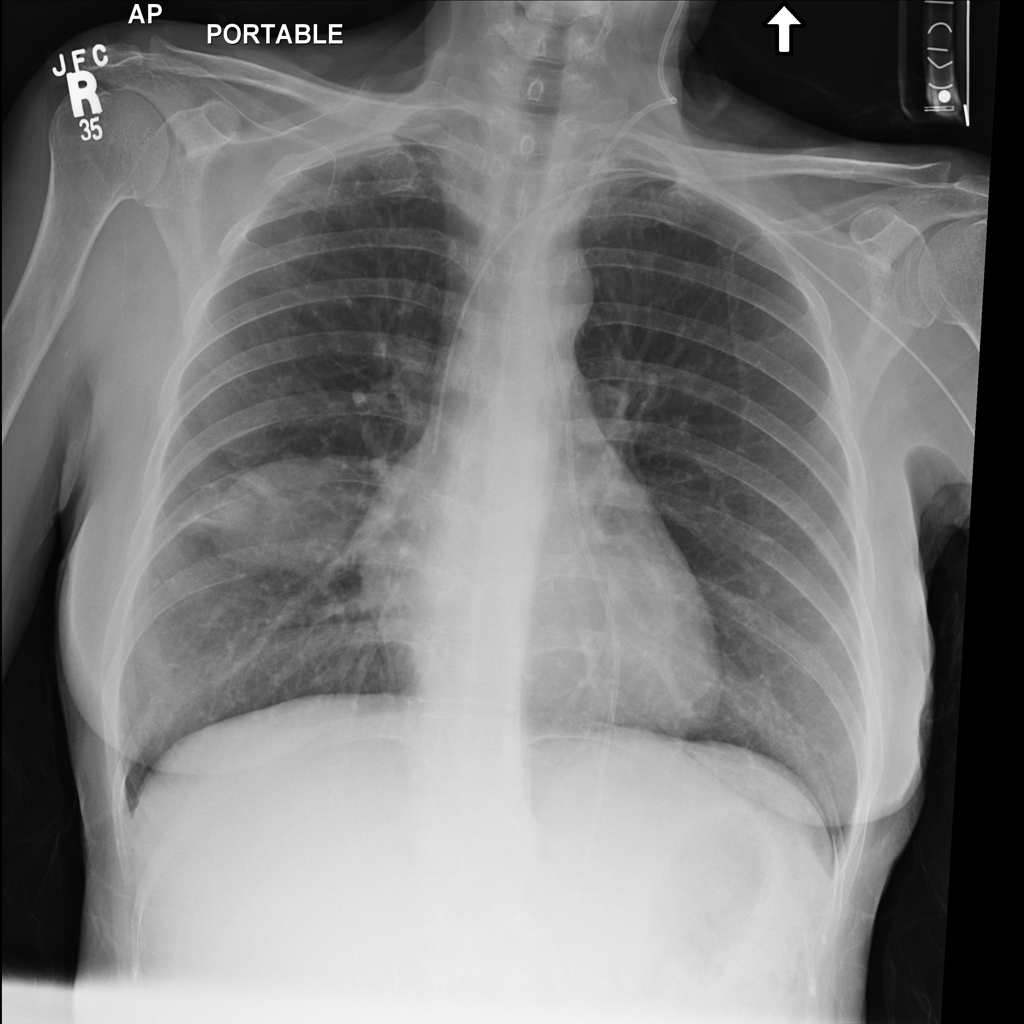

Mass

A mass is a larger focal opacity or lesion seen on the image. It is a descriptive finding that can have several causes and usually needs more imaging or clinical context to characterize.

PAT-C0E5 · IMG-001Mass

PAT-C0E5 · IMG-001

PA